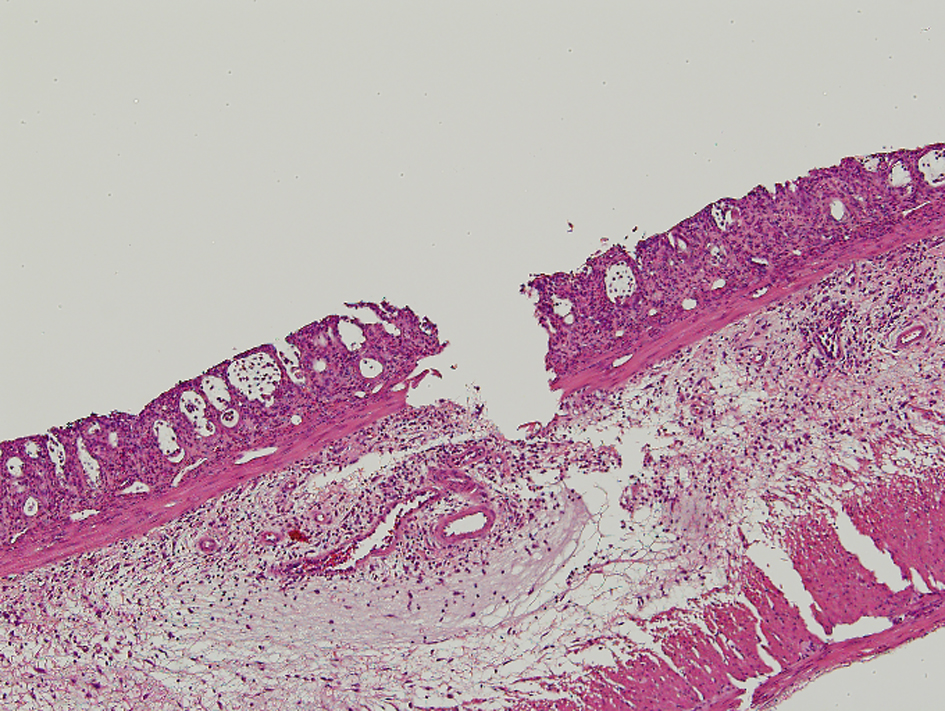

| The Morphological Mucosal Damage | ||

| The severity of proctitis was evaluated pathologically regarding the morphological mucosal damage, the degree of inflammation, and the depth of inflammation. The results were graded from 0 to 4, and then were compared. | ||

| 0 = Normal or minor alterations which could not be ascribed with certainly to radiation | ||

| 1 = Slight crypt change without loss of epithelium | ||

| 2 = Crypt change with loss of epithelium equaling less than one-half | ||

| 3 = Crypt change with loss of epithelium greater than one-half | ||

| 4 = Loss of epithelium through muscularis mucosa | ||